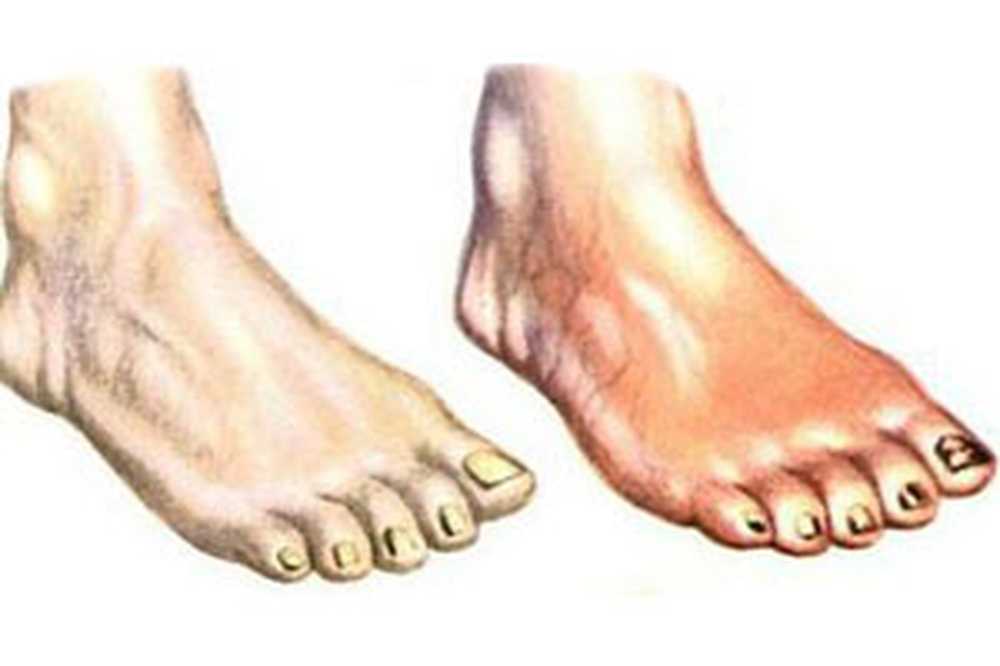

Изображения, связанные с атеросклерозом нижних конечностей и его лечением